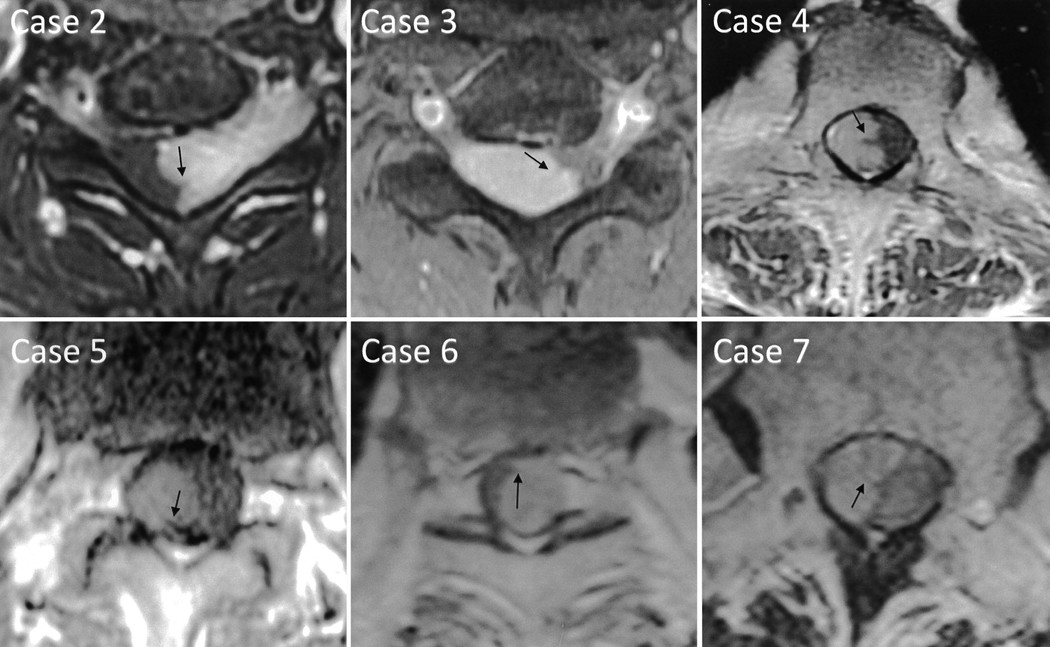

No.3黑色素型神经鞘瘤

神经鞘瘤的罕见亚型,由含黑色素的雪旺细胞构成

发病年龄较神经鞘瘤小(20-50 岁多见)

MRI 表现:由于黑色素含有自由基,T1WI 呈高信号,T2WI 呈低信号,是较具有特征的影像学表现

有时合并 Garney 综合征(抑癌基因 PRKA R1A 的丢失)

ce081637d93d5eb7d84b76511979b9ce.jpg

7718ea58d4cabe2dfae428d38daac676.jpg

腰椎管黑色素型神经鞘瘤:T1WI高信号,T2WI低信号,直观可见轻度强化